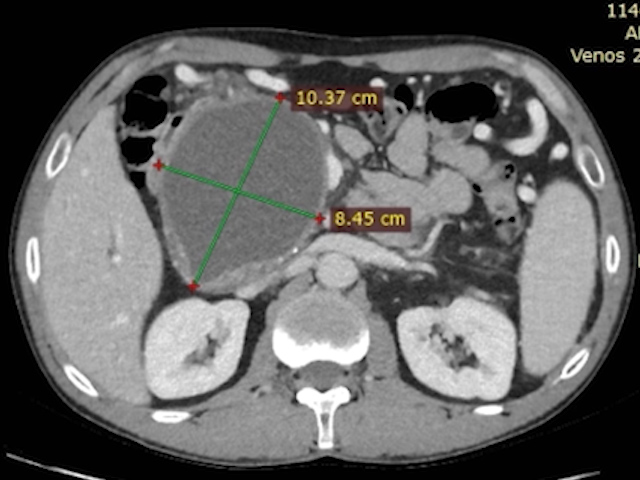

A 53-year-old man, smoker, with an episode of severe acute pancreatitis of uncertain etiology, complicated by a giant pancreatic collection, compressive at the gastric level, with necrosis inside (walled-off pancreatic necrosis) (Fig. 1-3).